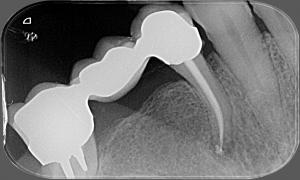

Pred zákrokom

Zapálený nerv so zakriveným koreňovým kanálikom

Po zákroku

Po zaplnení koreňových kanálikov aj so zaplnenou zakrivenou špičkou